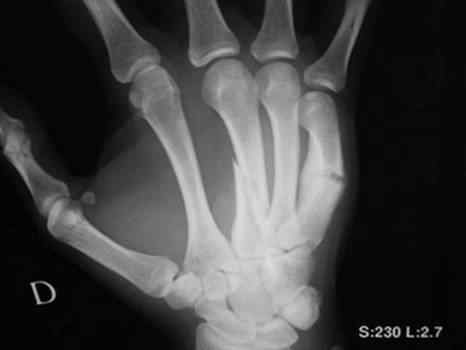

Косой перелом 3 пястной и повторный перелом 5 пястной кости на фоне старой мозоли

- со слов предыдущая травма около месяца назад. Какова тактика лечения ?

так вроде бы на 3-й укорочение небольшое есть, если не скрыпач, может и сойдет. Я бы лично дистракцию интраоперационно и закрыто спицами сделал. 5-ю можно и не трогать. если конечно не возиться с корригирующими остеотомиями и .т.п. Видать пациент, любитель подраться, больно уж перелом типичный на 5-й. Можно и гипс конечно на 4 недели. Все зависит от запросов пациента. Сделайте снимок здоровой, а лучше обе кисти на одну кассету рядом и измерьте длину 3-х костей. Все станет ясно, думаю.